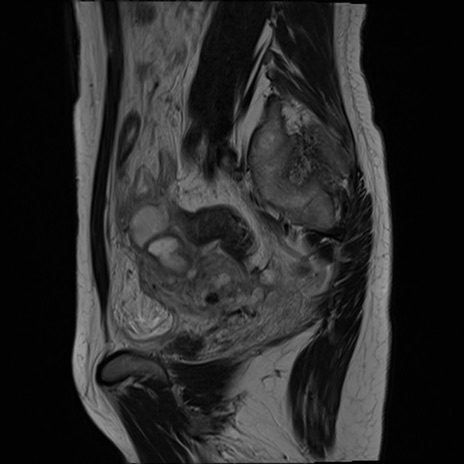

症例39 T2WI(矢状断像)

MRI(4日後)